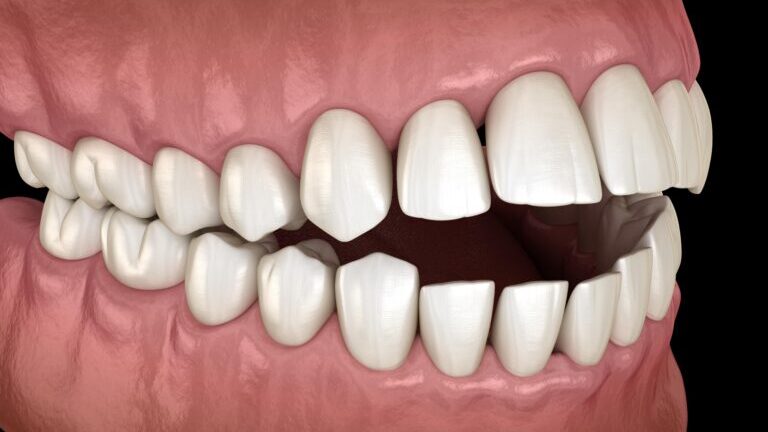

Czym jest elektrokoagulacja? Elektrokoagulacja to zabieg polegający na kontrolowanym wykorzystaniu prądu elektrycznego w celu zamknięcia naczyń krwionośnych oraz usunięcia zmienionych tkanek. W stomatologii metoda ta znajduje zastosowanie przede wszystkim w chirurgii i periodontologii. Stomatolog w nowoczesnej klinika stomatologiczna Kraków wykorzystuje…